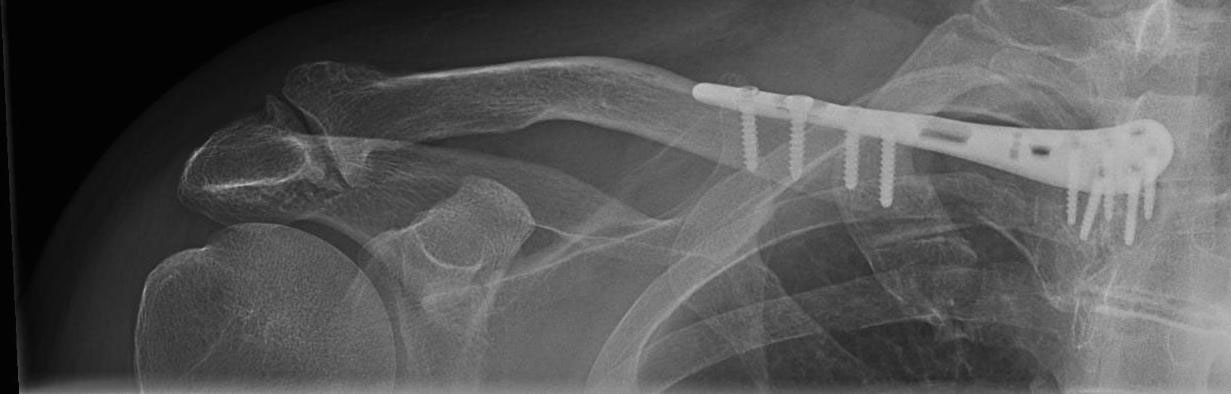

medial collar bone fracture one week after surgery – it shows the anatomical alignment and fixation of the collar bone using a long clavicle plate.

X-ray of medial collar bone fracture one week after surgery – it shows the anatomical alignment and fixation of the collar bone using a long clavicle plate.